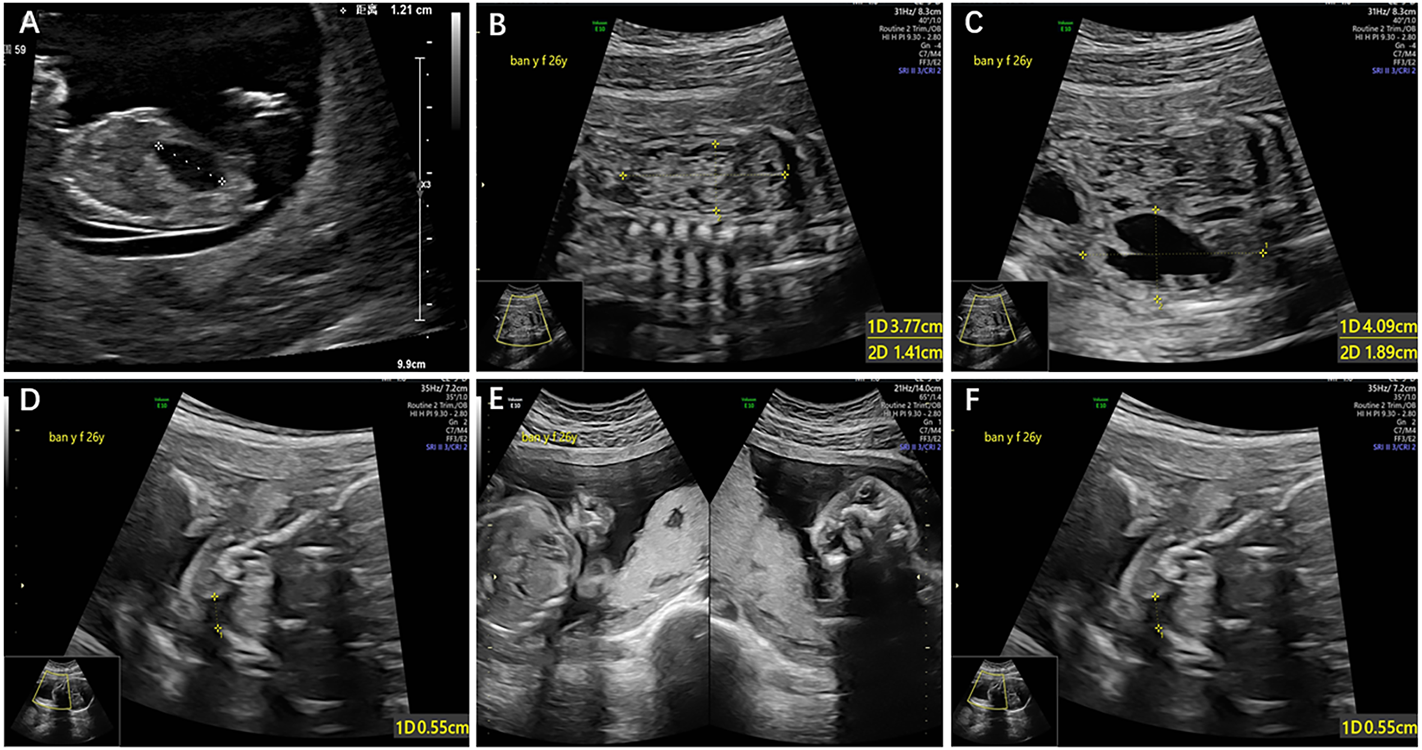

A 35-year-old G2P0 woman at the gestational age of 11 + 6 was referred to the prenatal diagnosis center of the International Peace Maternity and Child Health Hospital, due to an enlarged fetal bladder. The ultrasound showed a normal nuchal translucency (NT = 1.3 mm) and an enlarged bladder with the diameter of 12 mm (Figure 1A). It was her secondary pregnancy after one ectopic in 2019. The couple was not consanguineous, and the family history was unremarkable for any other known congenital anomalies or otherwise. After 1 week, a repeated ultrasound showed a slightly reduced bladder with a diameter of 10 mm. Considering the advanced maternal age and contingency of ultrasound findings, chorionic villus sampling (CVS) was then suggested. However, CVS could not be performed due to the posterior placenta. Non-invasive prenatal testing (NIPT) was conducted at 15 weeks of gestation, and the NIPT result was negative. At 17 weeks, the woman accepted amniocentesis and chromosome microarray analysis (CMA) as the first-line genetic testing. After 3 weeks, the CMA and karyotyping results were both normal. At 22 weeks, the routine fetal anomaly scan showed multiple structural abnormalities including the right multicystic kidney, left hydronephrosis, and cleft lip and palate (Figures 1B–F).

FIGURE 1

(A): Enlarged bladder with the diameter of 12Â mm, (B) right multicystic kidney, (C) left hydronephrosis with the width of 4Â cm, (D) cleft palate, (E) and (F)cleft lip.